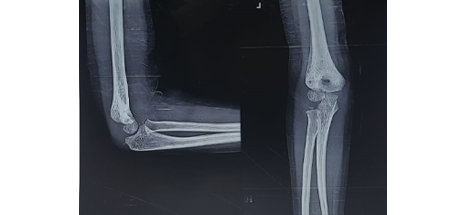

Supracondylar humerus fractures in Kids

Before

Pre Operative Lateral & AP view of Left elbow

After

2 month Post Operative AP and Lateral view of the left elbow

Full extension & full flexion of both the elbows